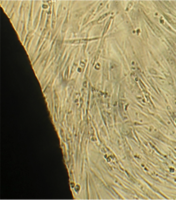

При наблюдении через 24 часа особых отклонений от контрольной культуры фибробластов мы не обнаружили.

Монослой оставался целостностным и равномерным на всей поверхности чашки Петри, клетки вблизи образца сохраняли характерное для культуры фибробластов взаимное расположение и направление роста (рис. 39).

Морфология их также соответствовала сроку роста: клетки веретеновидной формы с гомогенной цитоплазмой и центрально расположенным пузырьковидным ядром неплотно прилежали друг к другу и анастомозировали своими отростками.

В последующие сроки мы также не наблюдали каких-либо морфологических признаков воздействия имплантата на культуру фибробластов.

Клетки формировали равномерный монослой, плотность которого соответствовала сроку роста культуры после пассирования и не зависела от расстояния до образца (таб. 17).